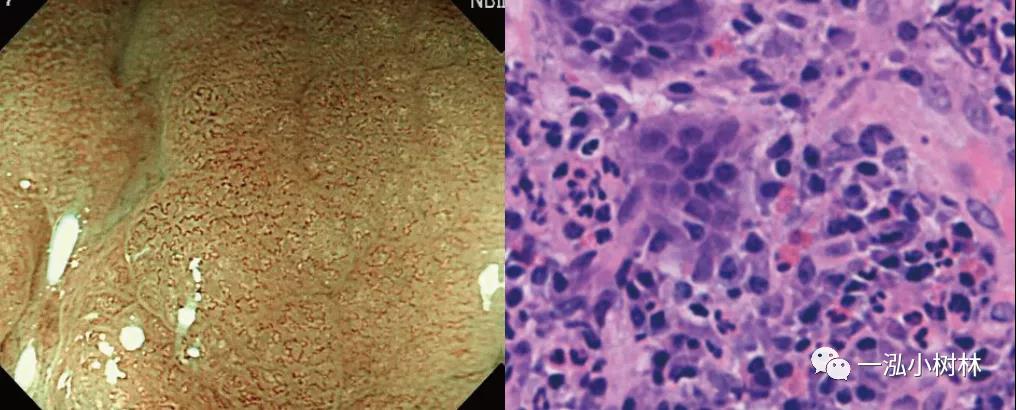

例1 17岁女性患者,嗜酸粒细胞性胃肠炎。

图1 嗜酸粒细胞性胃肠炎. 内镜:发现肠黏膜红斑、水肿、溃疡;病理:黏膜固有层中可以观察到多数(20个/高倍视野以上)的嗜酸性粒细胞的浸润。